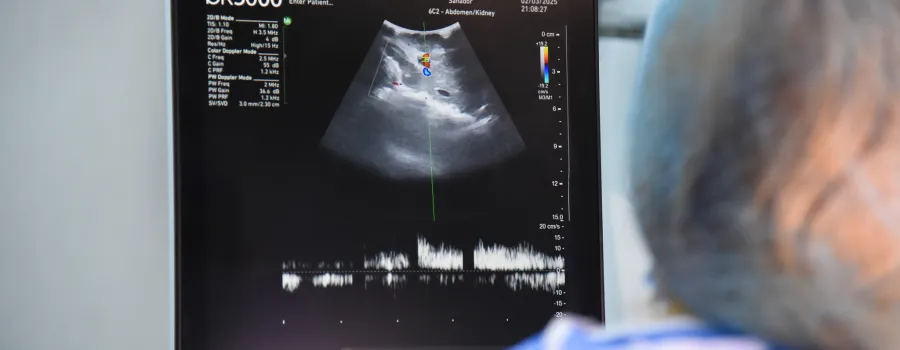

România a înregistrat un progres semnificativ în domeniul transplanturilor de organe în 2024, cu 84 de donatori în moarte cerebrală și aproape 300 de transplanturi realizate de la începutul anului.

Numai în ultimele două zile au fost realizate trei prelevări de organe și țesuturi în București, Satu Mare și Constanța.

Pe 28 noiembrie, la Spitalul Clinic de Urgență București (Floreasca) a avut loc o prelevare de organe de la un donator în vârstă de 77 de ani. În urma acesteia s-au realizat un transplant hepatic la Institutul Clinic Fundani și transplanturi de cornee la Spitalul Clinic de Urgențe Oftalmologice București și la Spitalul Universitar de Urgență București.

În aceeași zi, la Spitalul Județean de Urgență Satu Mare a fost efectuată o prelevare de la o donatoare de 73 de ani, aflată în moarte cerebrală în urma unui accident vascular cerebral. S-au realizat un transplant hepatic la Institutul Regional de Gastroenterologie-Hepatologie “Prof. Dr. Octavian Fodor” Cluj-Napoca și un transplant de cornee la București.

A doua zi, pe 29 noiembrie, la Spitalul Clinic Județean de Urgență Constanța a avut loc o prelevare de la un bărbat de 54 de ani. S-a realizat un transplant hepatic la Spitalul Sf. Maria București, însă rinichii nu au fost eligibili pentru transplant în urma testelor microbiologice.